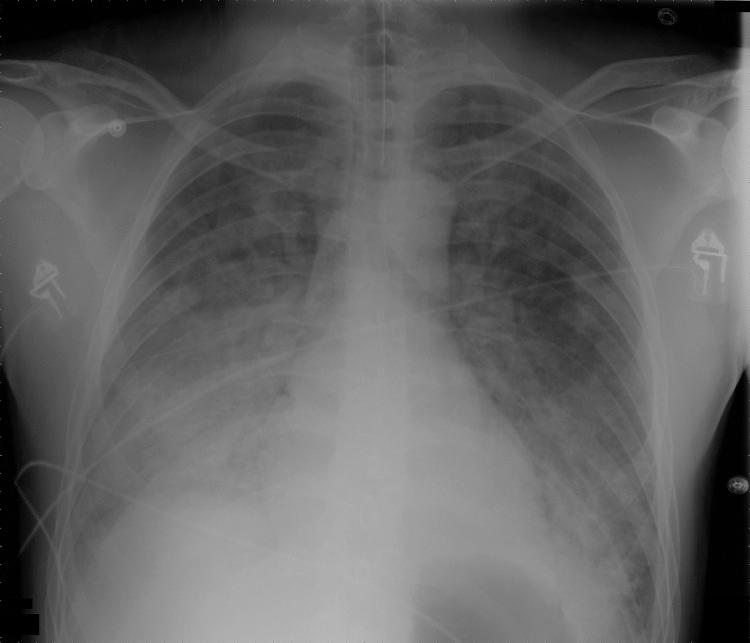

We encountered a case of severe murine typhus complicated by acute respiratory distress syndrome. To determine worldwide prevalence of such cases, we reviewed the literature and found that respiratory symptoms occur in ≈30% of murine typhus patients. In disease-endemic areas, murine typhus should be considered for patients with respiratory symptoms and fever.

我们遇到了一例严重的鼠型斑疹伤寒并发急性呼吸窘迫综合征的病例。为了确定此类病例在全球的患病率,我们查阅了文献,发现约30%的鼠型斑疹伤寒患者会出现呼吸道症状。在疾病流行地区,对于出现呼吸道症状和发热的患者应考虑鼠型斑疹伤寒。